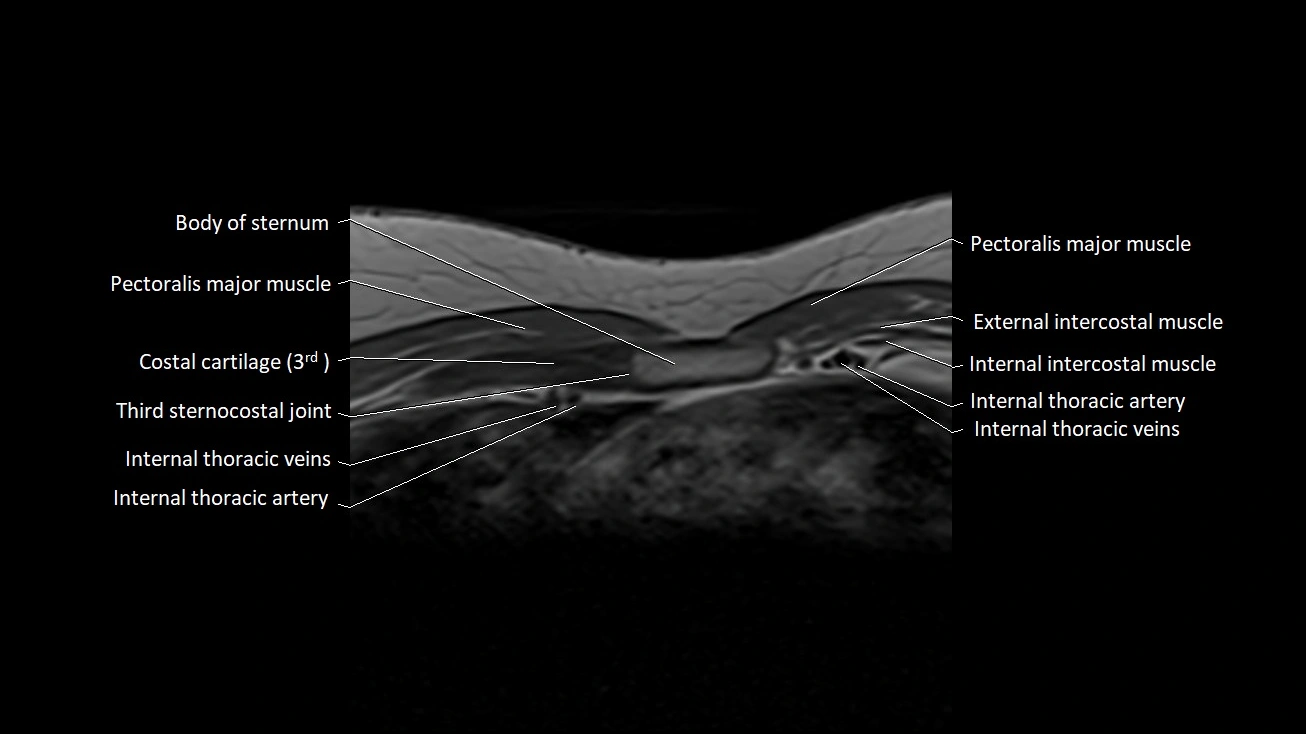

MRI Appearance

T1-weighted images

• Ligament appears as a low-signal (dark) linear band on the anterior aspect of the SC joint.

• Surrounding fat appears bright, providing contrast with the ligament.

• The clavicle and manubrium show normal cortical low signal with bright fatty marrow internally.

T2-weighted images

• Ligament remains low signal, darker than adjacent soft tissues.

• Articular disc and capsule appear as low-signal structures.

• Joint space fluid (if present physiologically) appears bright.

STIR

• Ligament maintains low-to-intermediate dark signal.

• Excellent for outlining adjacent soft-tissue planes due to fat suppression.

• Surrounding muscles and fascia demonstrate expected intermediate signal.

T1 Fat-Sat Post-Contrast

• Normal ligament shows no intrinsic enhancement, remaining uniformly low signal.

• Capsule may show minimal thin enhancement due to vascularized synovium.

• Fat suppression highlights the ligament’s dark, non-enhancing fibers.